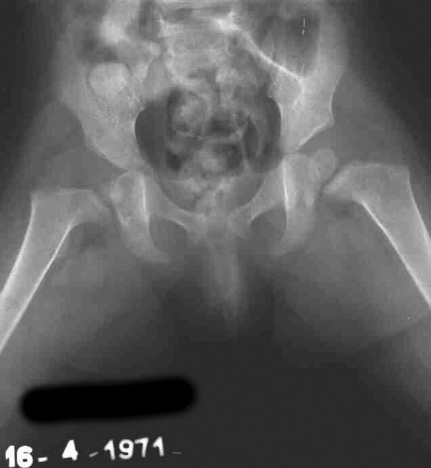

Alcuni mesi dopo, oltre ai disturbi della vascolarizzazione della testa femorale dx, si rende evidente un tetto inclinato o sfuggente. Di fronte al rischio di una perdita del risultato viene eseguita una tetto plastica. Si esegue una osteotomia del tetto che viene abbassato e reso orizzontale .

Il vuoto generato dalla correzione viene colmato con un cuneo di osso bovino. All’epoca non esisteva la banca dell'osso umano